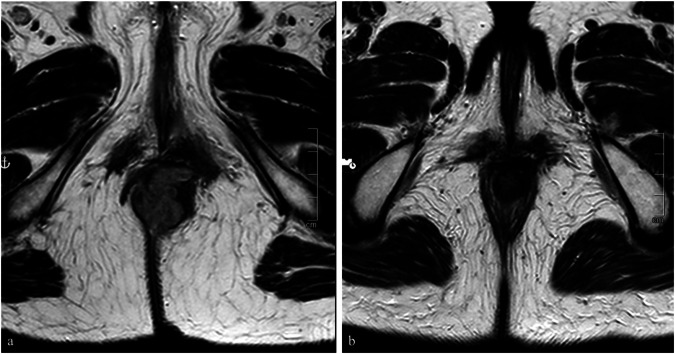

Methods: We manually annotated pretreatment T2-weighted turbo spin-echo images of 26 consecutive patients with stage III SCC of the anal canal treated with CRT at our institution from 2012 to 2022. Each patient was classified as complete response (CR, 17 patients), or non-complete response (non-CR, 9 patients) based on the absence or presence of residual disease at imaging and endoscopy after treatment. A total of 132 three-dimensional radiomic features were extracted for each patient and fed to a dedicated machine-learning classifier.